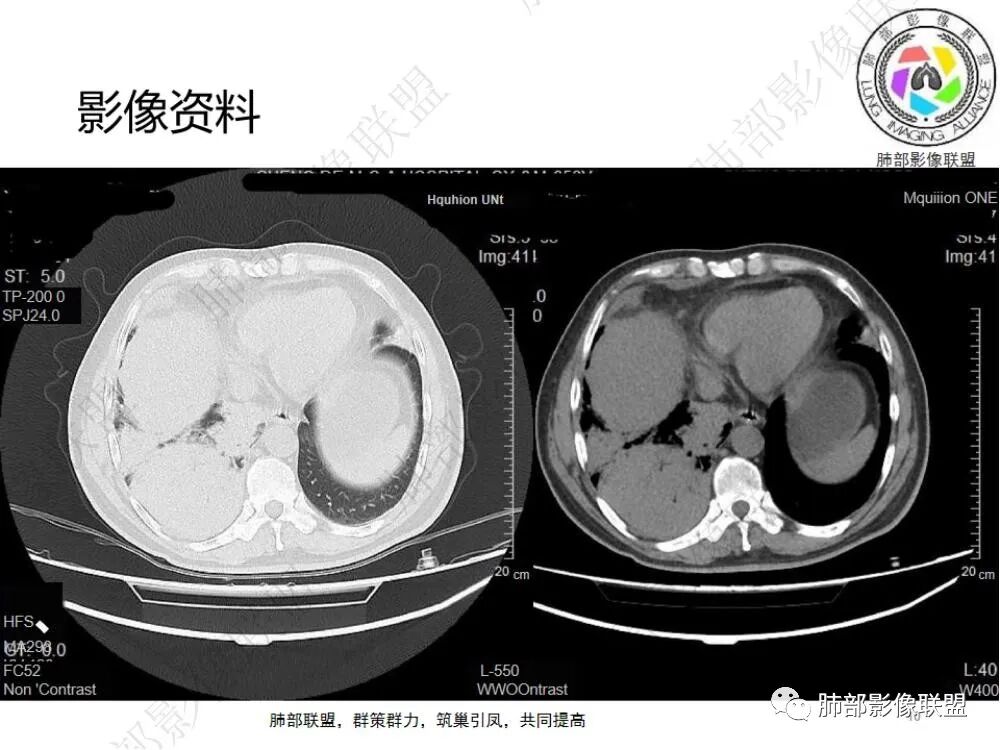

2.影像显示右肺上叶后段及右肺下叶较大范围实性密度为主片状影,边界可分辨,密度较均匀,隐约见小范围低密度(可疑液化区),未见钙化及气囊影。

4.右侧胸腔积液,多包裹局限。

6.一周后复查变化较为明显。肺部实变影有所吸收,但胸腔积液增加明显,包裹于侧胸壁、纵隔旁及叶间裂。注意右肺下叶因积液推压明显(可惜未能提供薄层图片及矢状位图片)。

7.扫描范围内肝顶叶未见异常低密度区。